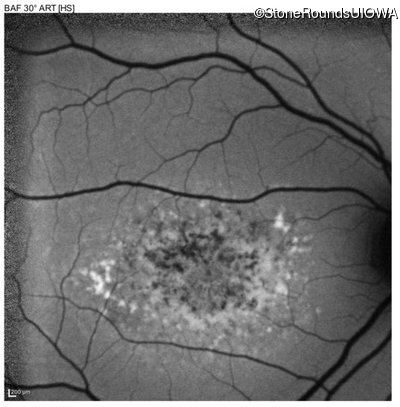

This 16 year old female first had difficulty seeing the blackboard at age 9. Her eye doctor at the time felt at the time that she was "faking it". More recently her eye doctor told her she would be blind by age 20 and suggested she get a seeing eye dog.

| AR Stargardt Disease | ABCA4 | Asp507Tyr GAT>TAT | IVS40+5 G>A | AR |